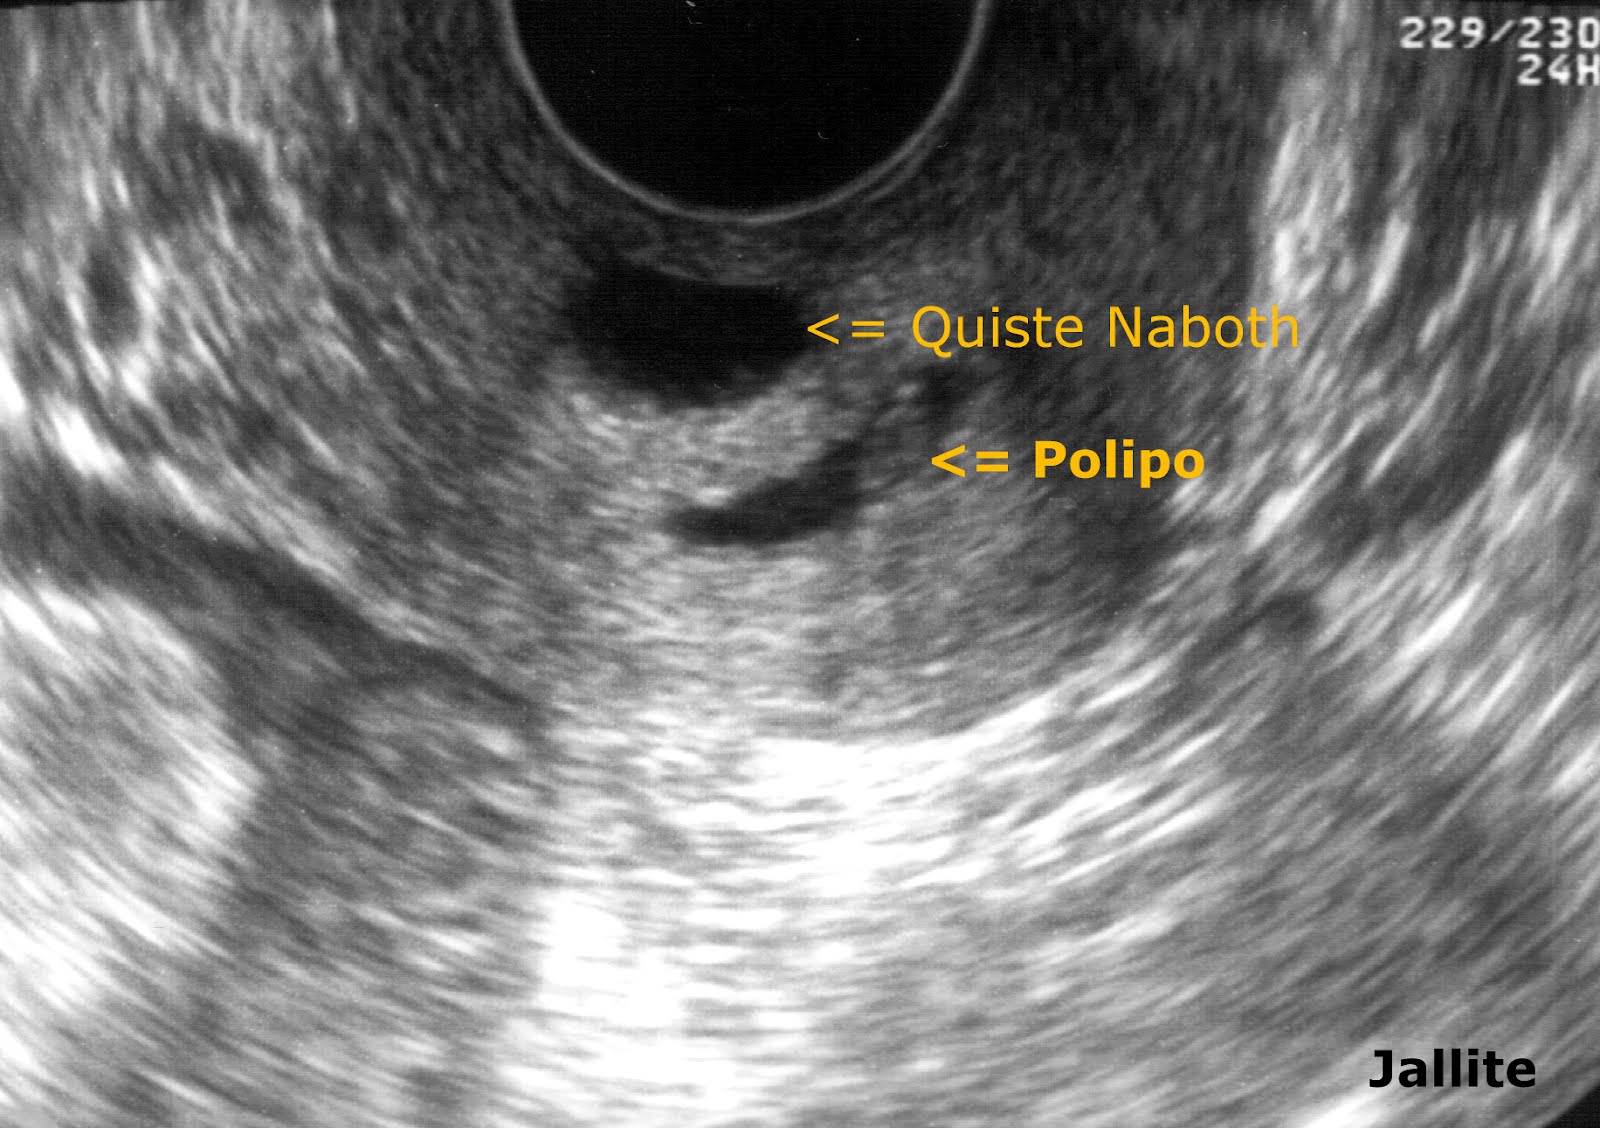

O Que Significa Pólipo Endocervical? Quando falamos em "pólipo endocervical", estamos nos referindo a esses crescimentos específicos que ocorrem no colo do útero. Geralmente, eles são benignos, mas, em alguns casos, podem se tornar malignos, o que é motivo de preocupação. Vamos discutir mais sobre esse aspecto posteriormente neste.. Há dois tipos deles: pólipo endometrial e pólipo endocervical. Neste artigo iremos explicar quais são suas características e a diferença entre eles. Os pólipos endometriais são, como o próprio nome sugere, as lesões que desenvolvem-se no endométrio e, portanto, localizam-se na cavidade uterina. Eles são constituídos a partir do.

O pólipo endometrial se caracteriza como uma saliência sólida localizada no endométrio (tecido que reveste o interior do útero), causada pelo crescimento anormal de células. O seu tamanho varia de 5 mm a 3 cm, podendo ser único ou múltiplo. Esse tipo de tumor benigno é mais comum na menopausa.. Se você recebeu recentemente um diagnóstico de pólipo no útero, fique tranquila. Na grande maioria das vezes, eles são alterações benignas com pequeno potencial de malignização. Pólipos uterinos são projeções da camada mais interna do útero, acima de sua superfície, sendo formados pelos mesmos tipos de célula, porém com um crescimento exagerado.